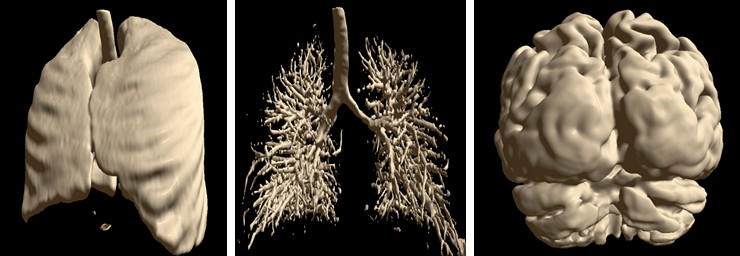

Isosurface Visualization¶

This method suits for bones, skin surface and segmented areas visualization. The base of this method is a search of intersection points between the rays corresponding to pixels and the isosurface. The user selects the level of the isosurface and the clipping plane position with sliders.

Automatic Segmentation¶

Special automatic segmentation methods are implemented for the lungs data and skull tissues separation from brain.

Semi-automatic Methods for Opening Areas of Interest¶

MRI Viewer has two methods for opening/selection areas of interest. The first one allows to clear volumetric data, which obstructs area of interest.

The second method allows to cut the area of interest from the source volume using deformable 3D triangle mesh.